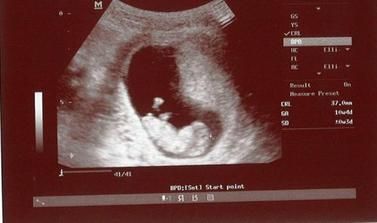

V decembri sme sa rozhodli vysadit antikoncepciu s tym, ze ak sa podari, tak sa stane... koncom decembra prisla menstruacia podla planu, ale ta januarova uz nedorazila.. ostali sme prekvapeni, ze sa podarilo tak skoro, kedze mame este len pred svadbou.. ale bez ohladu na to sme velmi stastni a tesime sa... 🙂